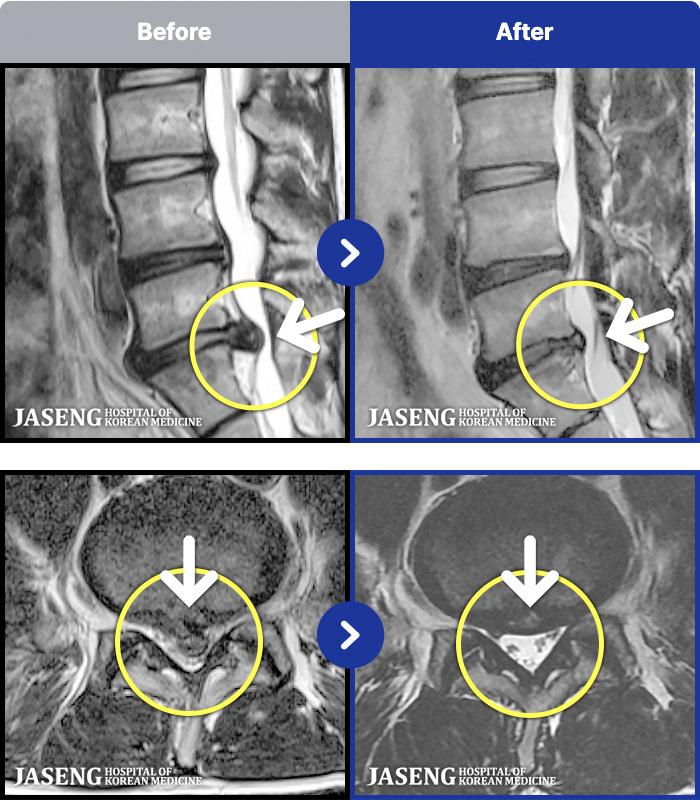

- MRI ġ

MRI ġ

1,237 MRI ũ ʸ Ȯϼ.